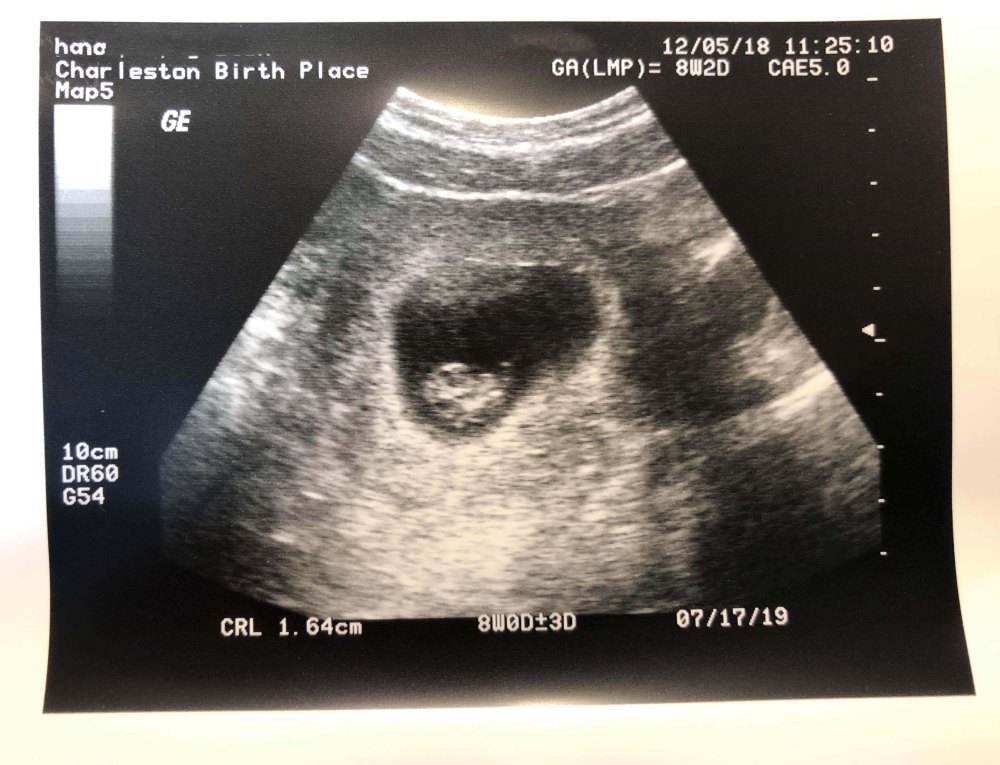

We definitely just want a healthy baby, but the early blood test said it might be a boy and as the mother of three daughters I do think it would be fun to buy some boy stuff! They were kind enough to video the first ultrasound for us and we got to see both the video and picture of our newest family member. The look on my daughters face when she heard the heartbeat was priceless.